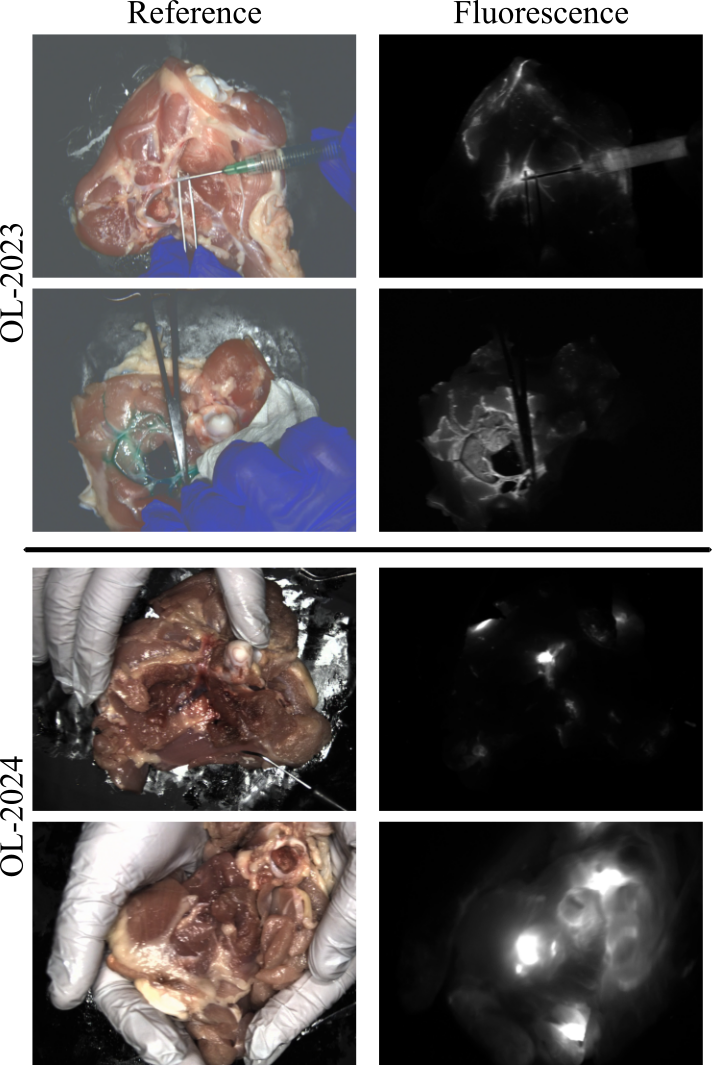

Figure 2: Dataset Example Images: Here we show two example images for both OL-2023 and OL-2024. OL-2023 focuses on vasculature where as OL-2024 focuses on local fluorescent regions.

OL-2024 and OL-Combined: The OL-2024 dataset contains 130 minutes of new mock surgical video, each video contains aligned RV, Rtvsubscriptsuperscript𝑅𝑣𝑡R^{v}_{t} and low-noise FV, Stsubscript𝑆𝑡S_{t} frames. OL-2024 has a focus on simulating surgeries similar to cancer resections or lymphatics while also introducing more challenging motion scenarios. We primarily inject ICG into muscle or fat causing irregular fluorescent blooming with substantial scattering, modeling surgeries with patches of embedded fluorescent tissue. Example images from OL-2023 and OL-2024 are shown in Fig. 2. Additionally, unlike OL-2023, videos in OL-2024 are largely contiguous, up 18 minutes, allowing testing of long range dependencies. While these long videos are not the focus of this work we expect them to be important in future work. We combine OL-2023 and OL-2024 into core dataset, OL-Combined which we split into a training and testing set.